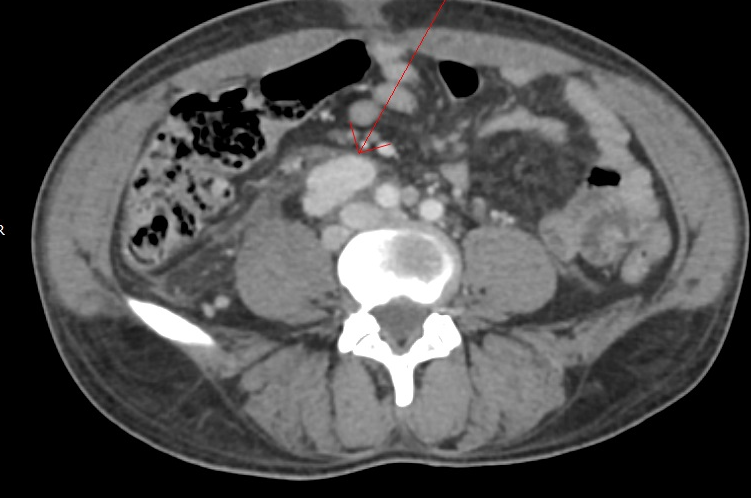

Para complementar a avaliação clínica, o ultrassom cervical é frequentemente realizado no consultório. Esse exame de imagem permite visualizar a estrutura interna do linfonodo, ajudando a diferenciar se ele tem aspecto benigno (reacional) ou suspeito. O exame é indolor, não invasivo e fornece informações valiosas para a conduta médica.

Quando os exames de imagem e o exame físico levantam suspeitas, ou quando a linfonodomegalia persiste sem causa aparente, o próximo passo pode ser a realização de uma biópsia. O procedimento mais comum é a Punção Aspirativa por Agulha Fina, conhecida como PAAF. Guiada por ultrassom, essa técnica retira algumas células do nódulo para análise laboratorial.